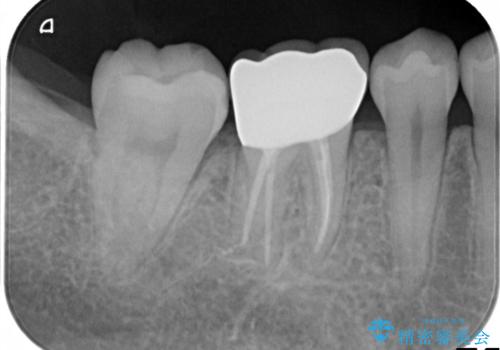

奥歯が痛い。根管治療~オールセラミッククラウン

検査の結果、神経は保存不可能と診断されたため、根管治療~オールセラミッククラウンによる治療を行いました。

- 13万円(根管治療別途)費用は治療当時の料金となります

根管治療を行った歯は破折のリスクが高まるので被せものによる修復が必要になります。